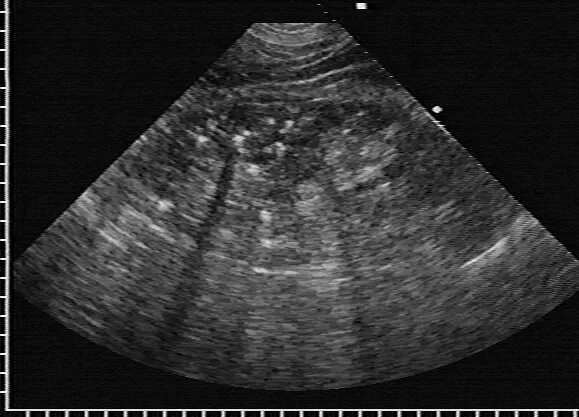

Нефрокальциноз почек на узи. синдром гиперэхогенных пирамид почек узи. медуллярная губчатая почка узи. гиперэхогенные пирамидки в почках на узи.

Синдром гиперэхогенных пирамид почек узи. микролиты в почках на узи. синдром гиперэхогенных пирамидок на узи. утолщение паренхимы почек на узи.

Синдром гиперэхогенных пирамид почек узи. медуллярный нефрокальциноз почек узи. губчатая почка узи картина. гиперэхогенные пирамидки в почках на узи.